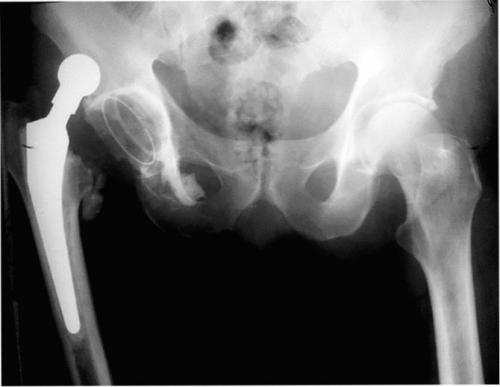

Стрелками указаны зоны инфекционного поражения.

- При протезном переломе (приводит к нестабильности).

Перелом импланта случается очень редко.